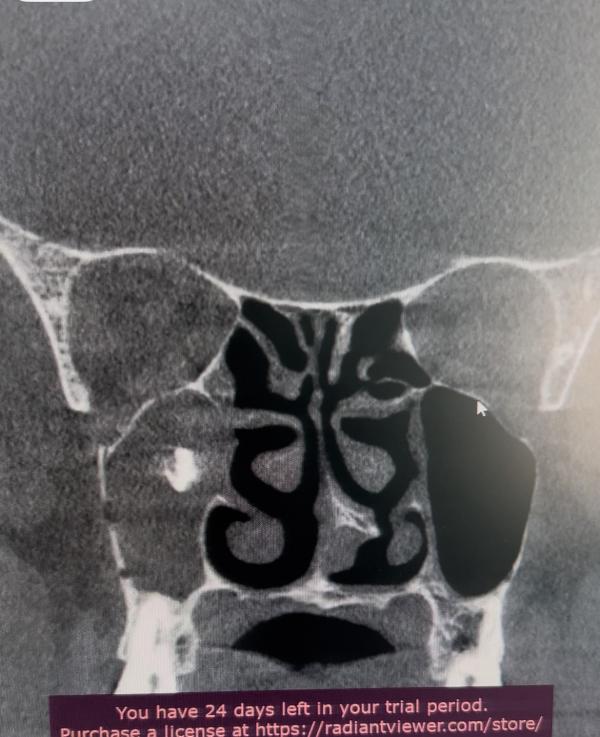

Не всегда синуситы это только про лор-врача. Иногда это совместная работа вместе со стоматологами (ЧЛХ).

На картинке правосторонний синусит с инородным телом в пазухе( а может уже и мицетома).

Здравствуйте! Значит у вас расположение материала не вызывающее воспаление в пазухе и оно не «плавает» в ней. Второй момент,возможно предмет лежит рядом с зубом (мне так сложно сказать) и его,в случае необходимости,удалит стоматолог. То есть вам не требуется обширное оперативное лечение,как в данном случае (я была бы рада,если это был пломбировочный материал 🥲)

Пломбировочный материал,отнюдь,не редкая находка в пазухах,но и не всегда несет последствия)